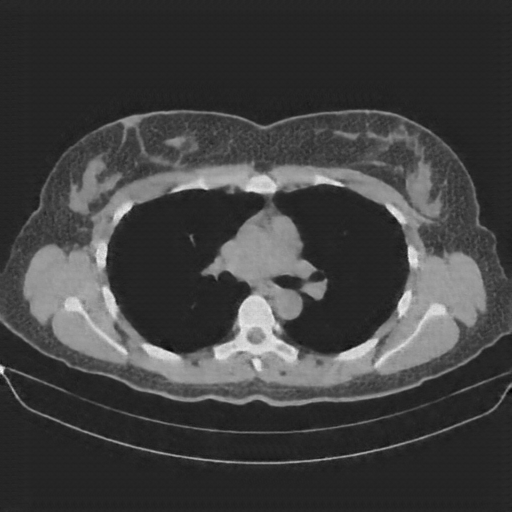

Image Grid

4Γ—3 grid: Rows show different image types (Original NATIVE, Reconstructed NATIVE, Original VENOUS, Generated VENOUS), Columns show windowing techniques (No Window, Lung Window, Mediastinum Window)

Lung window (WL -600, WW 1500 β†’ Low βˆ’1350, High +150)